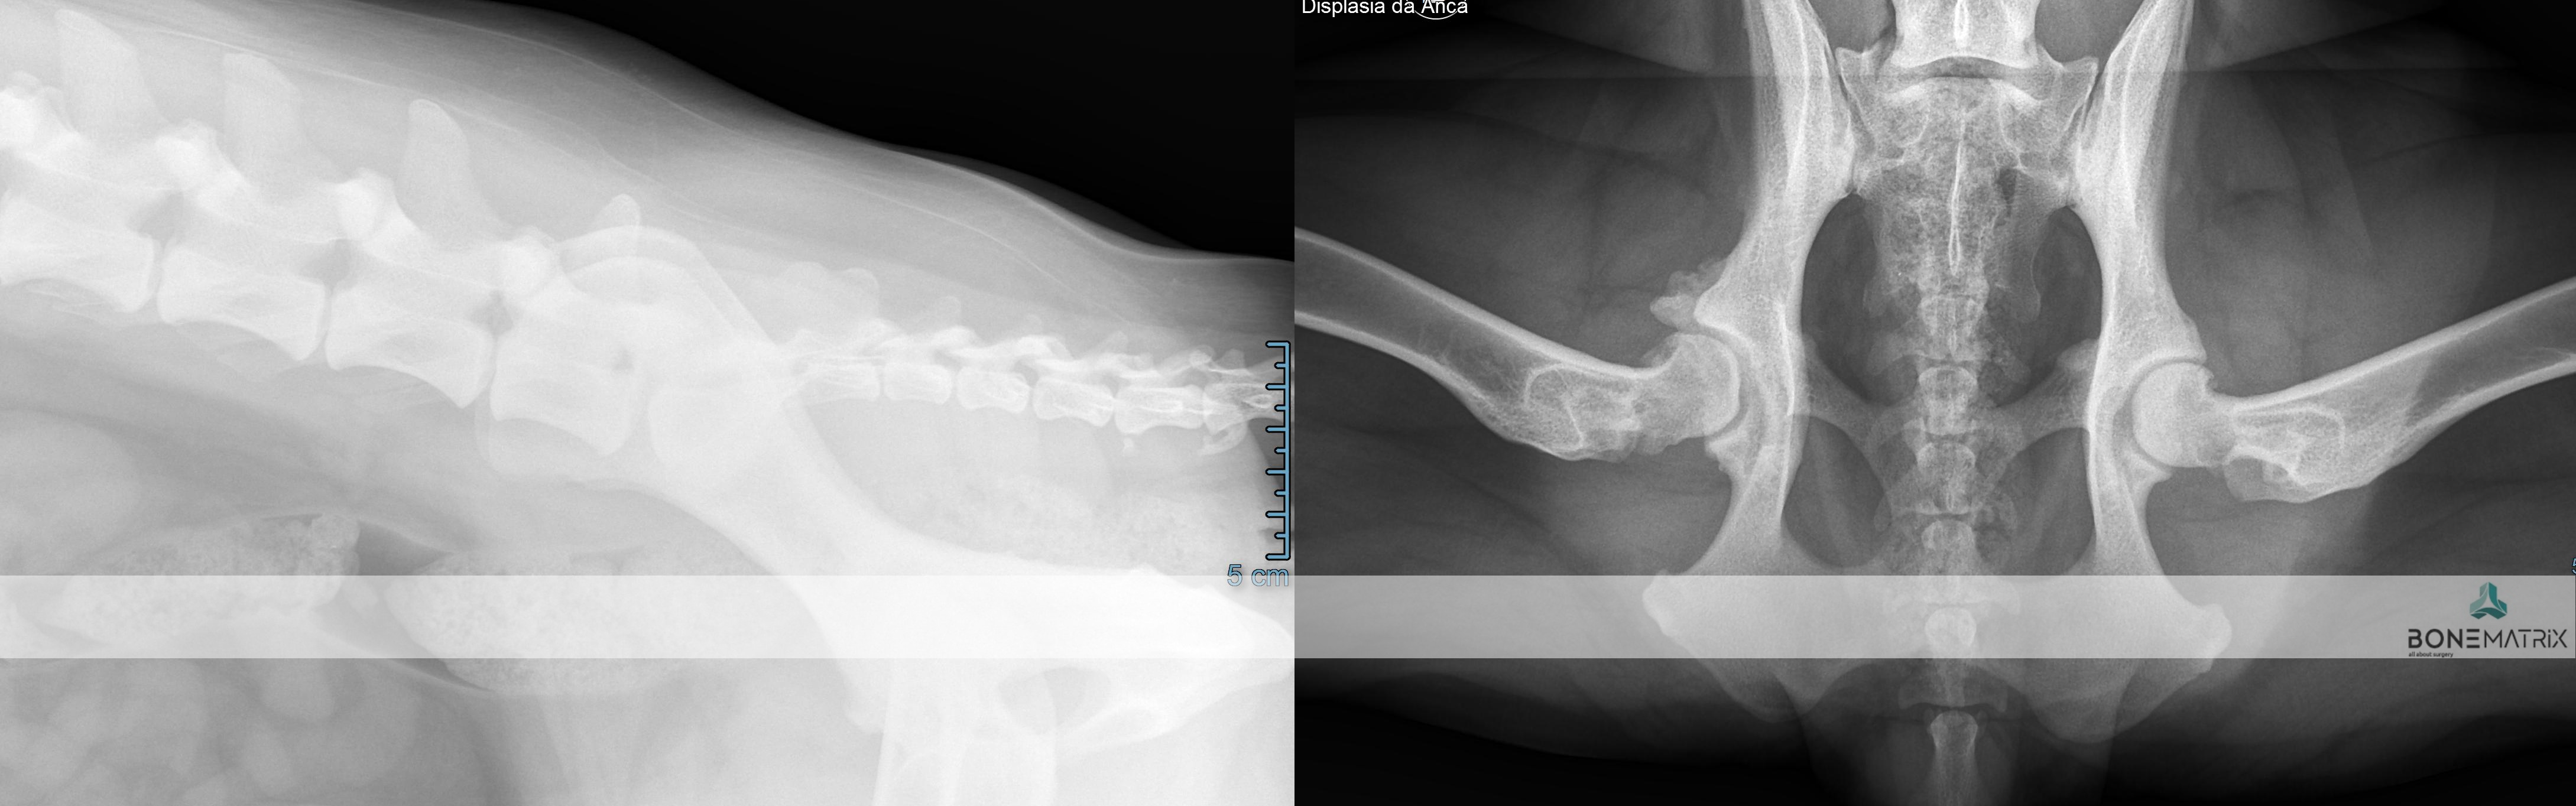

O que é?

A displasia de anca é uma patologia de desenvolvimento expressa na articulação coxo-femoral (entre o fémur e a pélvis). Esta é a doença ortopédica mais comum nos cães.

A sua origem é maioritariamente genética, podendo por vezes apresentar também uma influencia ambiental.

Como se desenvolve a doença de displasia de anca?

Inicialmente existe uma laxitude dos tecidos moles (capsula articular e musculatura envolvente) que permite juntamente com uma má cobertura da cabeça femoral pela componente óssea da pélvis (acetábulo). Estes fatores em conjunto levam à possibilidade de um movimento excessivo entre os componentes desta articulação, o que faz com que seja possível luxar cabeça femoral.

Esta luxação ocorrendo repetidamente leva ao desenvolvimento de alterações ósseas de ambas as componentes articulares que contribuem para a exacerbação da capacidade de luxação. Entrando assim num ciclo a capacidade de luxação leva a alterações articulares que permitem cada vez mais a luxação da articulação.

Esta movimentação dentro da articulação eventualmente leva ao desenvolvimento de um quadro de osteoartrite que conforme a severidade da doença se poderá apresentar também este com uma severidade correspondente.

Predisposição

Qualquer raça pode apresentar displasia de anca, contudo algumas são mais predispostas, nomeadamente as raças de porte grande a gigante, como Pastor Alemão, Newfoundland, raças Retriever e Rottweiller.

Como diagnosticar/ Sinais?

O diagnóstico de displasia de anca deve ser realizado idealmente antes dos 5 meses, daí a importância do despiste precoce da doença.

Uma vez que este seja detetado cedo na vida do animal poderão ser consideradas opções de tratamento preventivo. Na maioria destes casos os animais apenas apresentam laxitude articular, sendo com frequência assintomáticos clinicamente. Por este motivo a intervenção cirúrgica nestas idades impede que um animal que iria desenvolver a doença a desenvolva efetivamente ou então que desenvolva apenas um quadro de osteoartrite muito ligeiro, que possa ser gerido medicamente numa idade geriátrica.

O diagnóstico é feito com recurso a um estudo radiográfico de despiste de displasia de anca (este estudo pode ser realizado a partir dos 4 meses).

Com o decorrer da doença os animais podem apresentar sintomatologia associada que nos leva à suspeita do diagnostico, nomeadamente, claudicação, incapacidade de fazer determinados movimentos, incapacidade de realizar saltos, início de marcha "à coelho", dor articular, teste de Ortolani e Barden positivos (avaliações especificas de exame ortopédico direcionadas para esta doença).

Qual o tratamento indicado?

O tratamento indicado depende da idade do paciente e das características estudadas da articulação.

Quando a idade do paciente o permite e este se revela um bom candidato, pode em idade imatura, ser realizada uma DPO (double pelvic osteotomy), sendo este um procedimento preventivo do desenvolvimento de displasia de anca.

Quando o animal é adulto a única opção de tratamento curativa passa pela prótese total de anca (THR). Esta permite substituir a articulação afetada na sua totalidade e devolver a qualidade de vida ao paciente até ao fim da vida dele.

Em pacientes adultos, onde não se prevê um agravamento do quadro para além de ligeiro poderá ser ponderado o tratamento médico, onde na realidade não se está a praticar nenhum processo curativo, mas sim um mascarar de dor/desconforto ligeiro com recurso a medicação anti-inflamatória/analgésica.